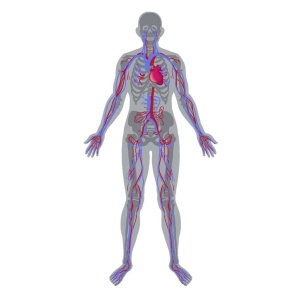

혈관(Blood vessel)

혈액은 우리 몸의 전신을 순환하며 영양분을 공급하고 노폐물을 옮기는 역할을 하는데, 이때 혈액이 지나가는 통로가 혈관입니다. 혈관은 동맥, 모세혈관, 정맥으로 나눌 수 있습니다. 동맥은 심장에서 나와 산소가 풍부한 혈액을 전신으로 보내주는 역할을 하며, 모세혈관은 조직세포에 산소와 영앙분을 공급하고 이산화탄소와 노폐물을 수거해갑니다. 정맥은 조직에서 걸러진 이산화탄소와 노폐물을 다시 심장으로 모이게 하는 역할을 합니다.

위치우리 몸의 전신에 분포하고 있습니다.

혈관은 심장에서 나오는 산소화된 혈액을 우리 몸 전신의 장기와 조직으로 운반하고, 온몸을 거친 혈액을 다시 심장으로 보내는 역할을 합니다.